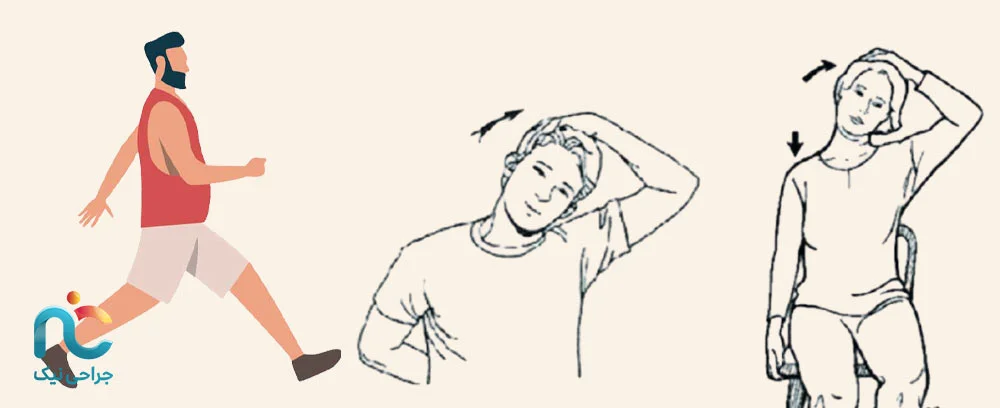

یکی از اولین و مهمترین کارها، فعالیت بدنی مناسب است. تمرینات سبک و هدفمند میتوانند عضلات گردن، شانه و پشت را تقویت کنند و انعطافپذیری ستون فقرات گردنی را افزایش دهند. این تمرینها باعث میشوند فشار کمتری به دیسک و عضلات هنگام عمل وارد شود و پس از آن راحتتر حرکت کنید. برای این منظور میتوانید هر روز چند دقیقه کشش گردن و شانه انجام دهید، سر خود را به آرامی به طرفین، جلو و عقب حرکت دهید و بعد از هر حرکت چند ثانیه مکث کنید. تمرینات تقویتی سبک برای عضلات پشت و شانه نیز مفید است؛ استفاده از کشهای مقاومتی سبک یا وزنههای خیلی کم کمک میکند عضلات عمقی قویتر شوند. همچنین، پیادهروی روزانه ۲۰ تا ۳۰ دقیقه جریان خون بافتها را افزایش داده و آمادگی عمومی بدن را بالا میبرد. در طول روز مراقب وضعیت نشستن و ایستادن خود باشید، گردن و پشت را بیش از حد خم نکنید و بهصورت مرتب وضعیت بدن را تغییر دهید تا فشار ثابت روی گردن نباشد. مطالعات نشان دادهاند که برنامههای تمرینی قبل از عمل میتوانند طول بستری را کوتاهتر کنند و عوارض پس از عمل را کاهش دهند (منبع).

هر روز چند دقیقه بنشینید، چشمانتان را ببندید، نفسهای عمیق و آرام بکشید: مثلاً چهار ثانیه نفس بکشید، هفت ثانیه نگه دارید، و هشت ثانیه بازدم کنید. این کار روی کاهش ضربان قلب، کاهش فشار خون و آرامش مغز تأثیر دارد. خواب بهتر، کمتر شدن درد پس از عمل و بهبود سریعتر را به همراه دارد (منبع).

۳. ورزشهای تقویتی گردن

بعد از جراحی، عضلات اطراف گردن باید دوباره قدرت بگیرند تا بتوانند از مهرهها پشتیبانی کنند. بدون عضلات قوی، کوچکترین فشار ممکن است دوباره درد را برگرداند. بهتر است تمرینات خود را زیر نظر پزشک یا فیزیوتراپ شروع کنید. تمرینهایی مثل فشار دادن پیشانی به کف دست، حرکت آرام گردن به راست و چپ، یا کشش ملایم شانهها به عقب، جریان خون را بهبود میدهند و التهاب را کاهش میدهند. وقتی احساس کردید توانتان بیشتر شده، میتوانید فعالیتهایی مثل پیادهروی یا شنا را هم اضافه کنید تا بدن در کل وضعیت پایدارتری پیدا کند.